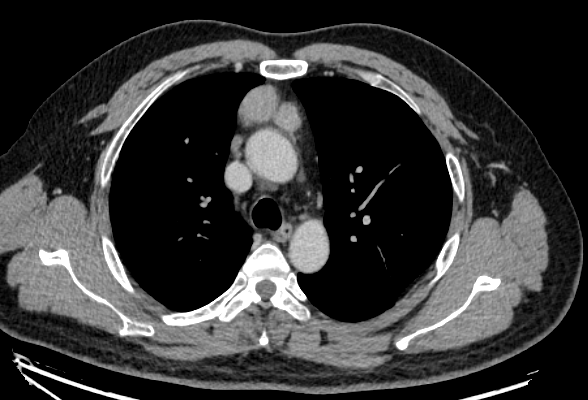

毛某,女59歲,2023年11月因咳嗽外院胸部CT檢查示縱隔肺門(mén)多發(fā)淋巴結(jié)性質(zhì)待排。外院建議進(jìn)一步明確病理,患者及家屬比較抗拒病理穿刺檢查。于2023年12月我院中醫(yī)門(mén)診求診,再次建議完善病理后給予針對(duì)性治療拒絕,要求中醫(yī)藥治療。于是給予中醫(yī)辨證益氣化痰散結(jié)立法加減治療。治療近半年,患者于2024年6月初我院門(mén)診復(fù)查同層面對(duì)比縱隔淋巴結(jié)明顯縮小。患者目前繼續(xù)觀察治療中。